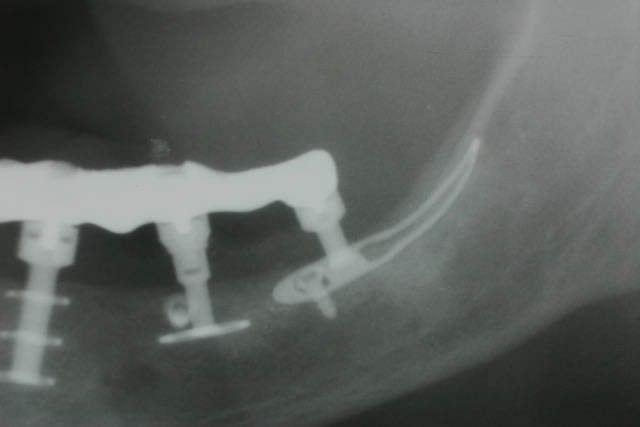

Tenez

voici les clichés de contrôle à 2 ans post op

Pépé

Pas possible car

1. déjà en échec sur les deux cylindres qui ont été posés

ds une crête trop étroite et sont divergeants donc la probabilité d en poser 5 bien parallèles

2. crête étroite en lame de couteau devant donc possible d y poser des triples disk bien parallèles

3. derrière crête plate où un amovible glisse comme une bille ds un bol

4. certains patients veulent des molaires et ne peuvent pas se contenter de prothèses courtes avec extension distale et stt pas si larrière est très résorbé comme c est le cas ici car l os reste inactif à cet endroit ( ou en tt cas moins activé )

En échec non pas sur les implants mais sur la prothèse qui n apportait pas satidfaction..car les implants étaient ds des axes trop divergeants ( piège des crêtes étroites )

Les pins sont des vis d ostéosynthèse placées pour empêcher l intempestive langue de pousser sur les pileirs pdt les 48 h de fabrication des dents fixes

Aucune transfo nécessaire : vissage à plat comme on appelle cela